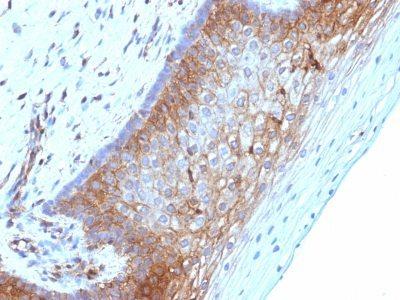

Positive Control

HL-60 or HeLa cells. Melanomas and Lymphoma. Carcinoma of Stomach, Cervix, Endometrial, Kidney or Colon.

Flow, intracellular (verified)|IF (verified)|IHC, FFPE (verified)|WB (verified)

Higher concentration may be required for direct detection using primary antibody conjugates than for indirect detection with secondary antibody|Immunofluorescence: 0.5-1 ug/mL|Immunohistology formalin-fixed 0.5-1 ug/mL|Staining of formalin-fixed tissues requires boiling tissue sections in 10 mM citrate buffer, pH 6.0, for 10-20 min followed by cooling at RT for 20 minutes|Flow Cytometry 0.5-1 ug/million cells/0.1 mL|Optimal dilution for a specific application should be determined by user